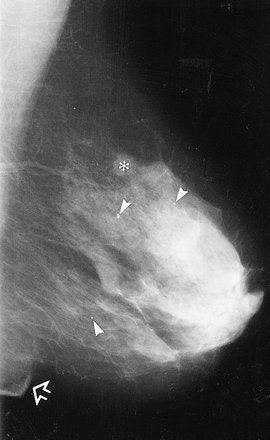

MLO images of the left breast in one patient. With (a) MC and (b) BC, the inframammary fold (open arrow) is depicted. A larger amount of the whole breast is depicted in b, on the basis of the positions of the three calcifications (arrowheads) and the round opacity (*). In addition, a cutaneous fold (solid arrows) is present in the axilla in a. Sardanelli F, Zandrino F, Imperiale A, et al, "Breast biphasic compression versus standard monophasic compression in x-ray mammography," Radiology 2000; 217:576-580.